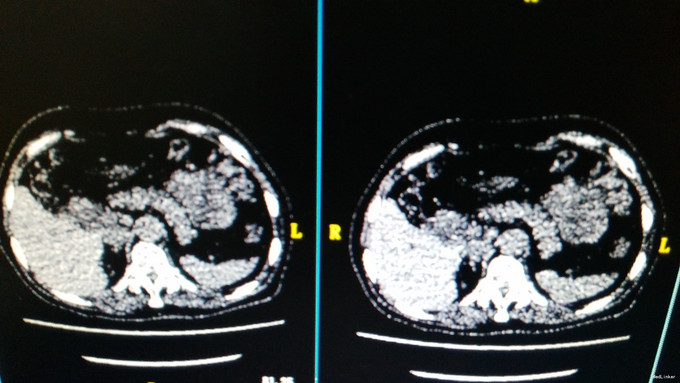

体格检查:神志清楚,表情较淡漠,反应迟钝,能正确回答问题。毛发稀疏,腋毛、阴毛脱落,眉毛稀疏。 入院后完善相关检查: 皮质醇节律: 8:00 15:00 24:00 COR(nmol/L): 455.8 232.9 102.0 ACTH(pg/ml): 10.92 11.21 6.69 糖耐量-胰岛功能测定: 0分 30分 60分 120分 180分 240分 300分 葡萄糖(mmol/L) : 4.84 8.52 7.82 5.70 9.28 6.15 5.30 C肽(pmol/L): 757.45 3327.86 4465.4 2382.0 2521.14 1513.0 胰岛素(mIU/L): 10.28 106.90 112.6 17.07 64.58 21.62 9.87 胰岛素原(pg/ml): 185.28 406.38 678.25 608.88 697.69 639.78 糖尿病抗体系列:血清抗胰岛素自身抗体测定IAA 6.57IU/mL,血清抗谷氨酸脱羧酶抗体测定GAD 8.89IU/mL。 饥饿试验 血糖:4.05mmol/L 胰岛素:5.73mIU/L C肽:286.14pmol/L 胰岛素原:163.21pg/mL 胰岛素释放指数:胰岛素/血糖÷18=0.078 胰腺CT灌注(64排):胆道低位梗阻,梗阻于胆总管胰段,邻近管壁增厚.

患者饥饿试验时胰岛素、C肽、胰岛素原、胰岛素释放指数均未明显升高,未出现低血糖发作症状,目前不支持胰岛细胞瘤的诊断。以上化验\试验及影像学不支持胰岛素瘤的诊断.建议继续完善MRCP等检查明确胆道梗阻病因,但家属要求出院回当地医院继续检查.